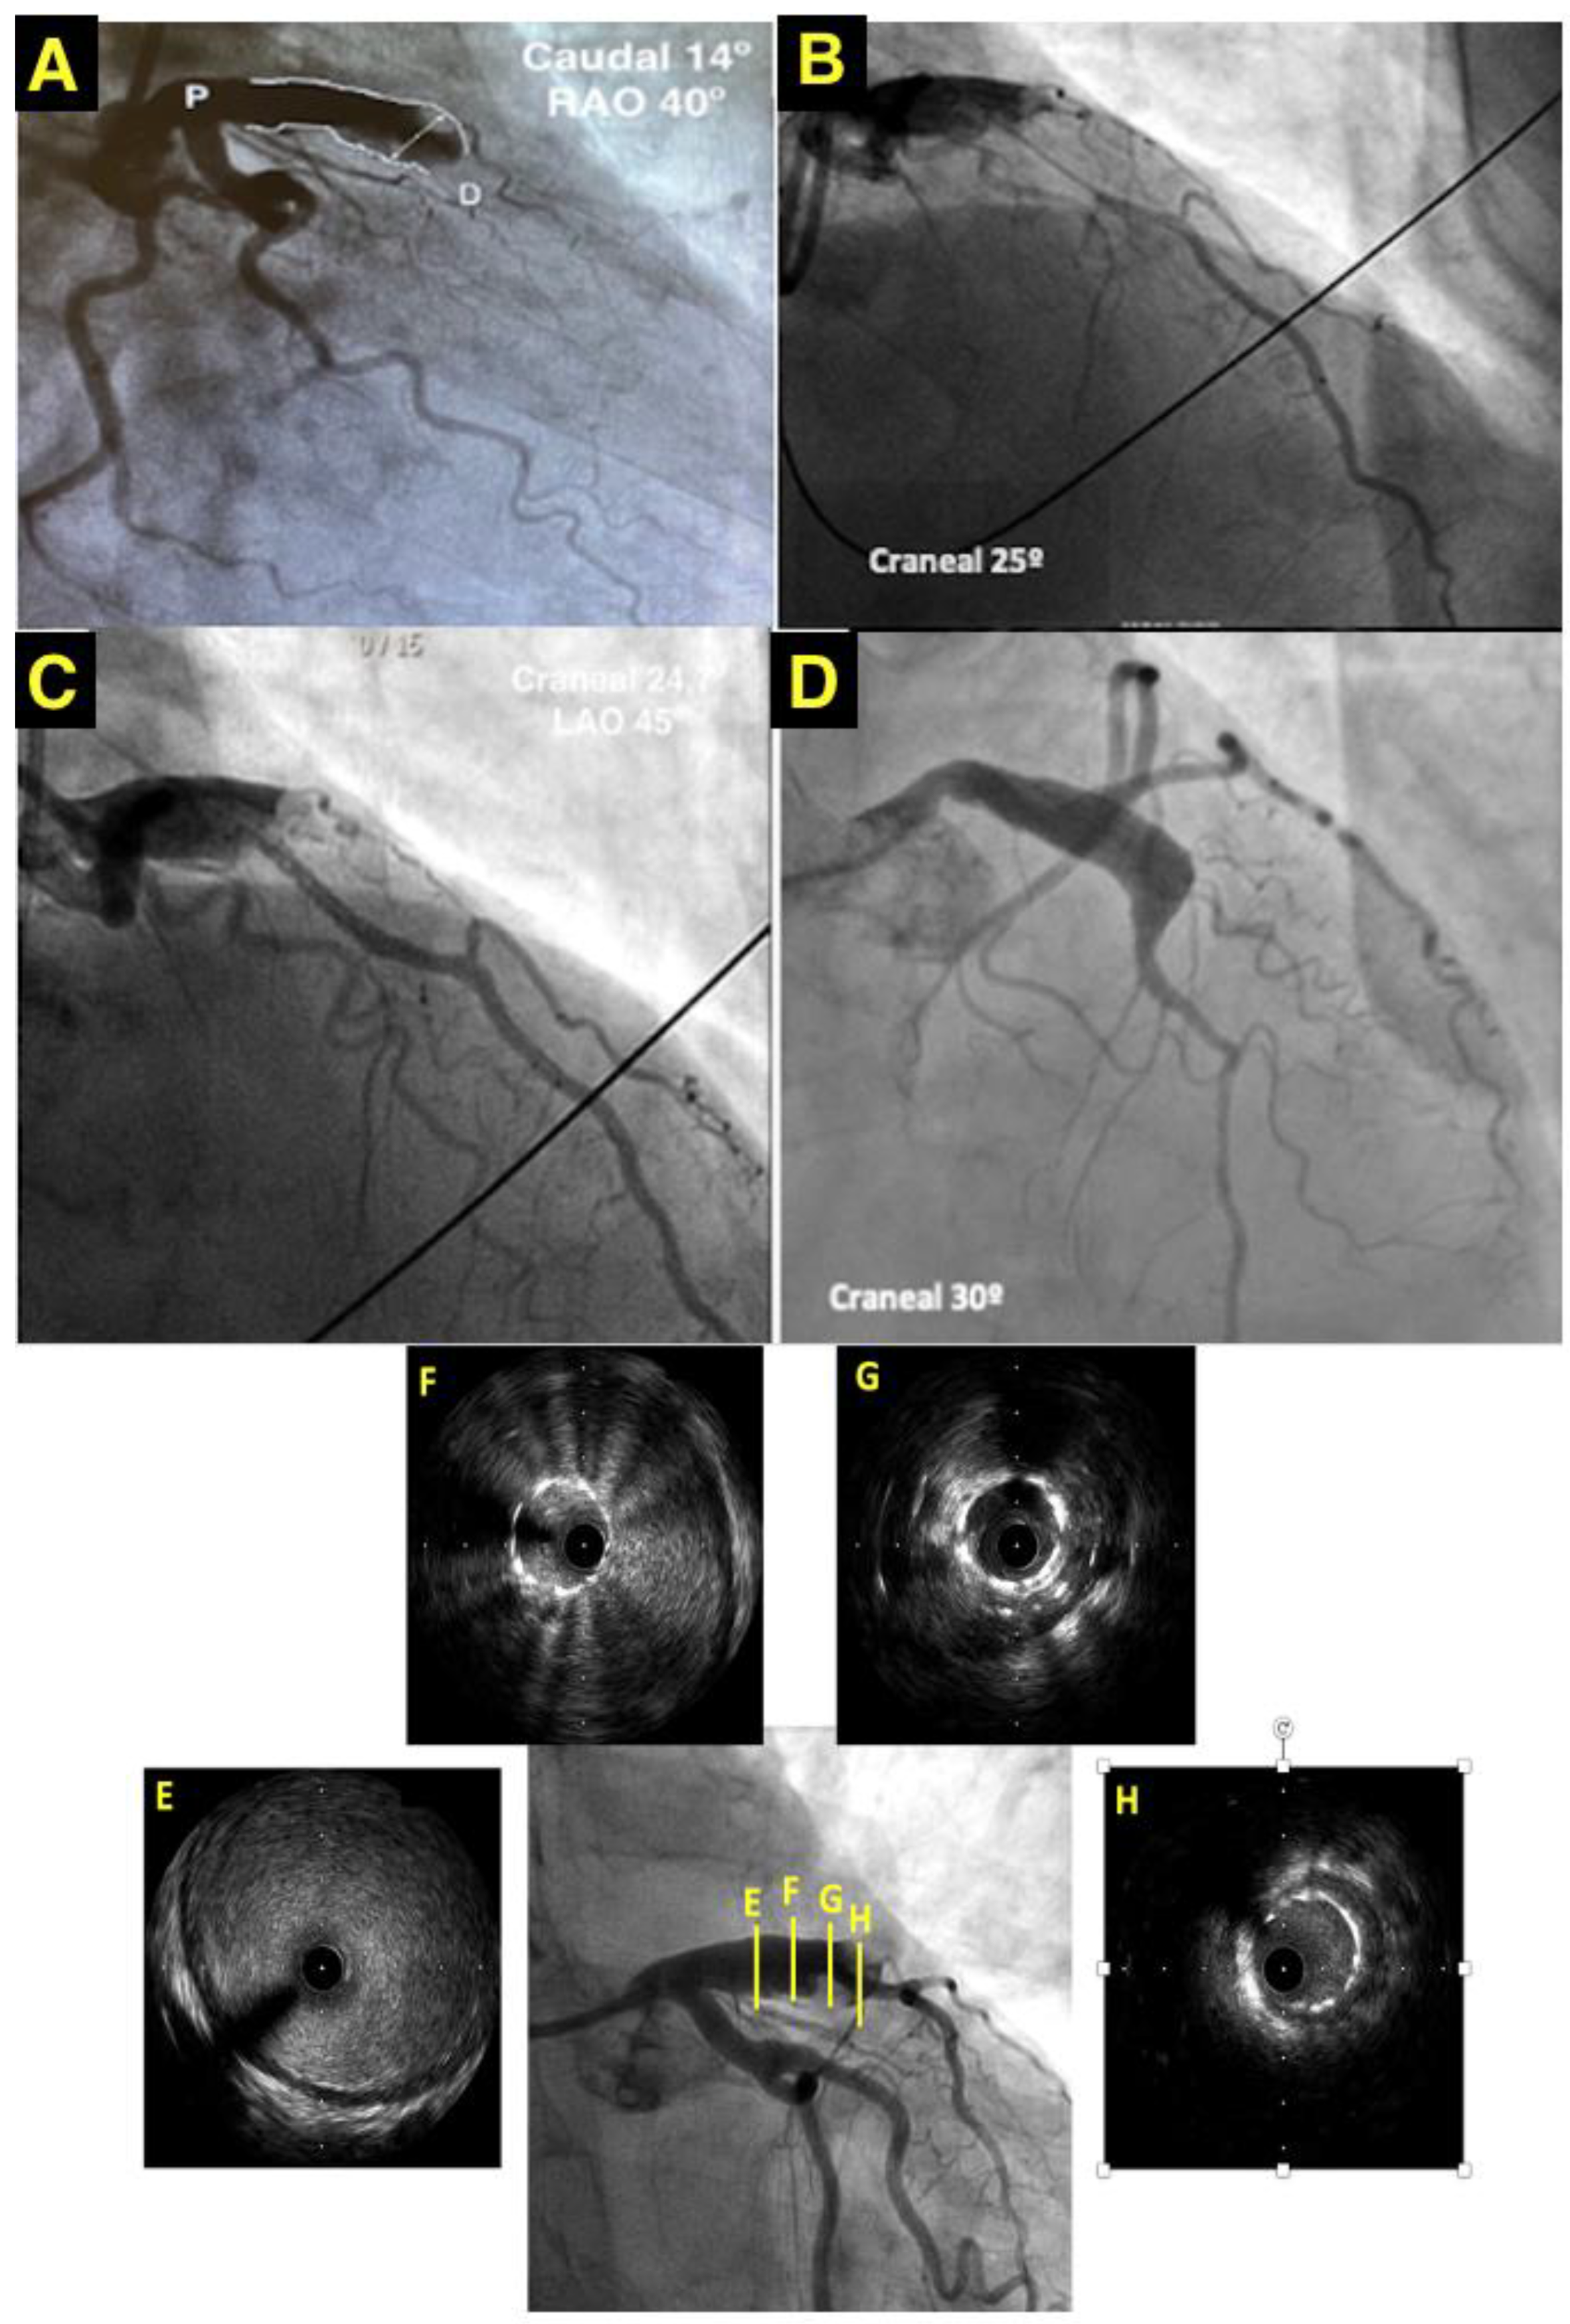

A coronary computed tomography angiography (CCTA) was carried out one year later to check the permeability of the stent. The CCTA showed a 7.6 × 9.8 mm diameter aneurysm (Figure 2A,B). The stent was “floating” in the aneurysm (Figure 2C,D) with a preserved distal flow. Acquired and congenital thrombophilia disorders were carried out. Clopidogrel was discontinued and patient agreed to be anticoagulated endlessly. The patient did not have angina two years after STEMI.

Figure 2. CCT. (A) GCA (black arrow) lateral view on three-dimensional volume-rendered CCT. (B) Coronal view of GCA (black arrow) with dimensions in CCT. Axial (C) and sagittal oblique (D) view of GCA showing the stent “floating” in the aneurysm with a “funnel”-like form disposition.